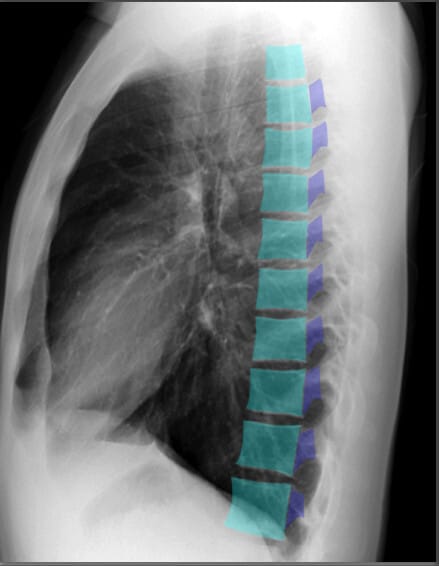

| 척추체 (Vertebral Bodies) |

| ✅ 척추체는 정상적으로 크기와 모양이 균일해야 하며, 압박 골절이나 골 용해 소견이 있으면 병적 상태를 고려해야 합니다. |

| 추궁근 (Pedicles) |

| ✅ 추궁근은 척추의 일부로, 좌우 대칭적으로 나타나야 합니다. 종양이나 감염으로 인해 변형되거나 소실될 경우 병리적 상태를 의심할 수 있습니다. |

하늘색이 Vertebral bodies, 파란색 (코발트 블루)가 Pedicles| 기관 (Trachea) |